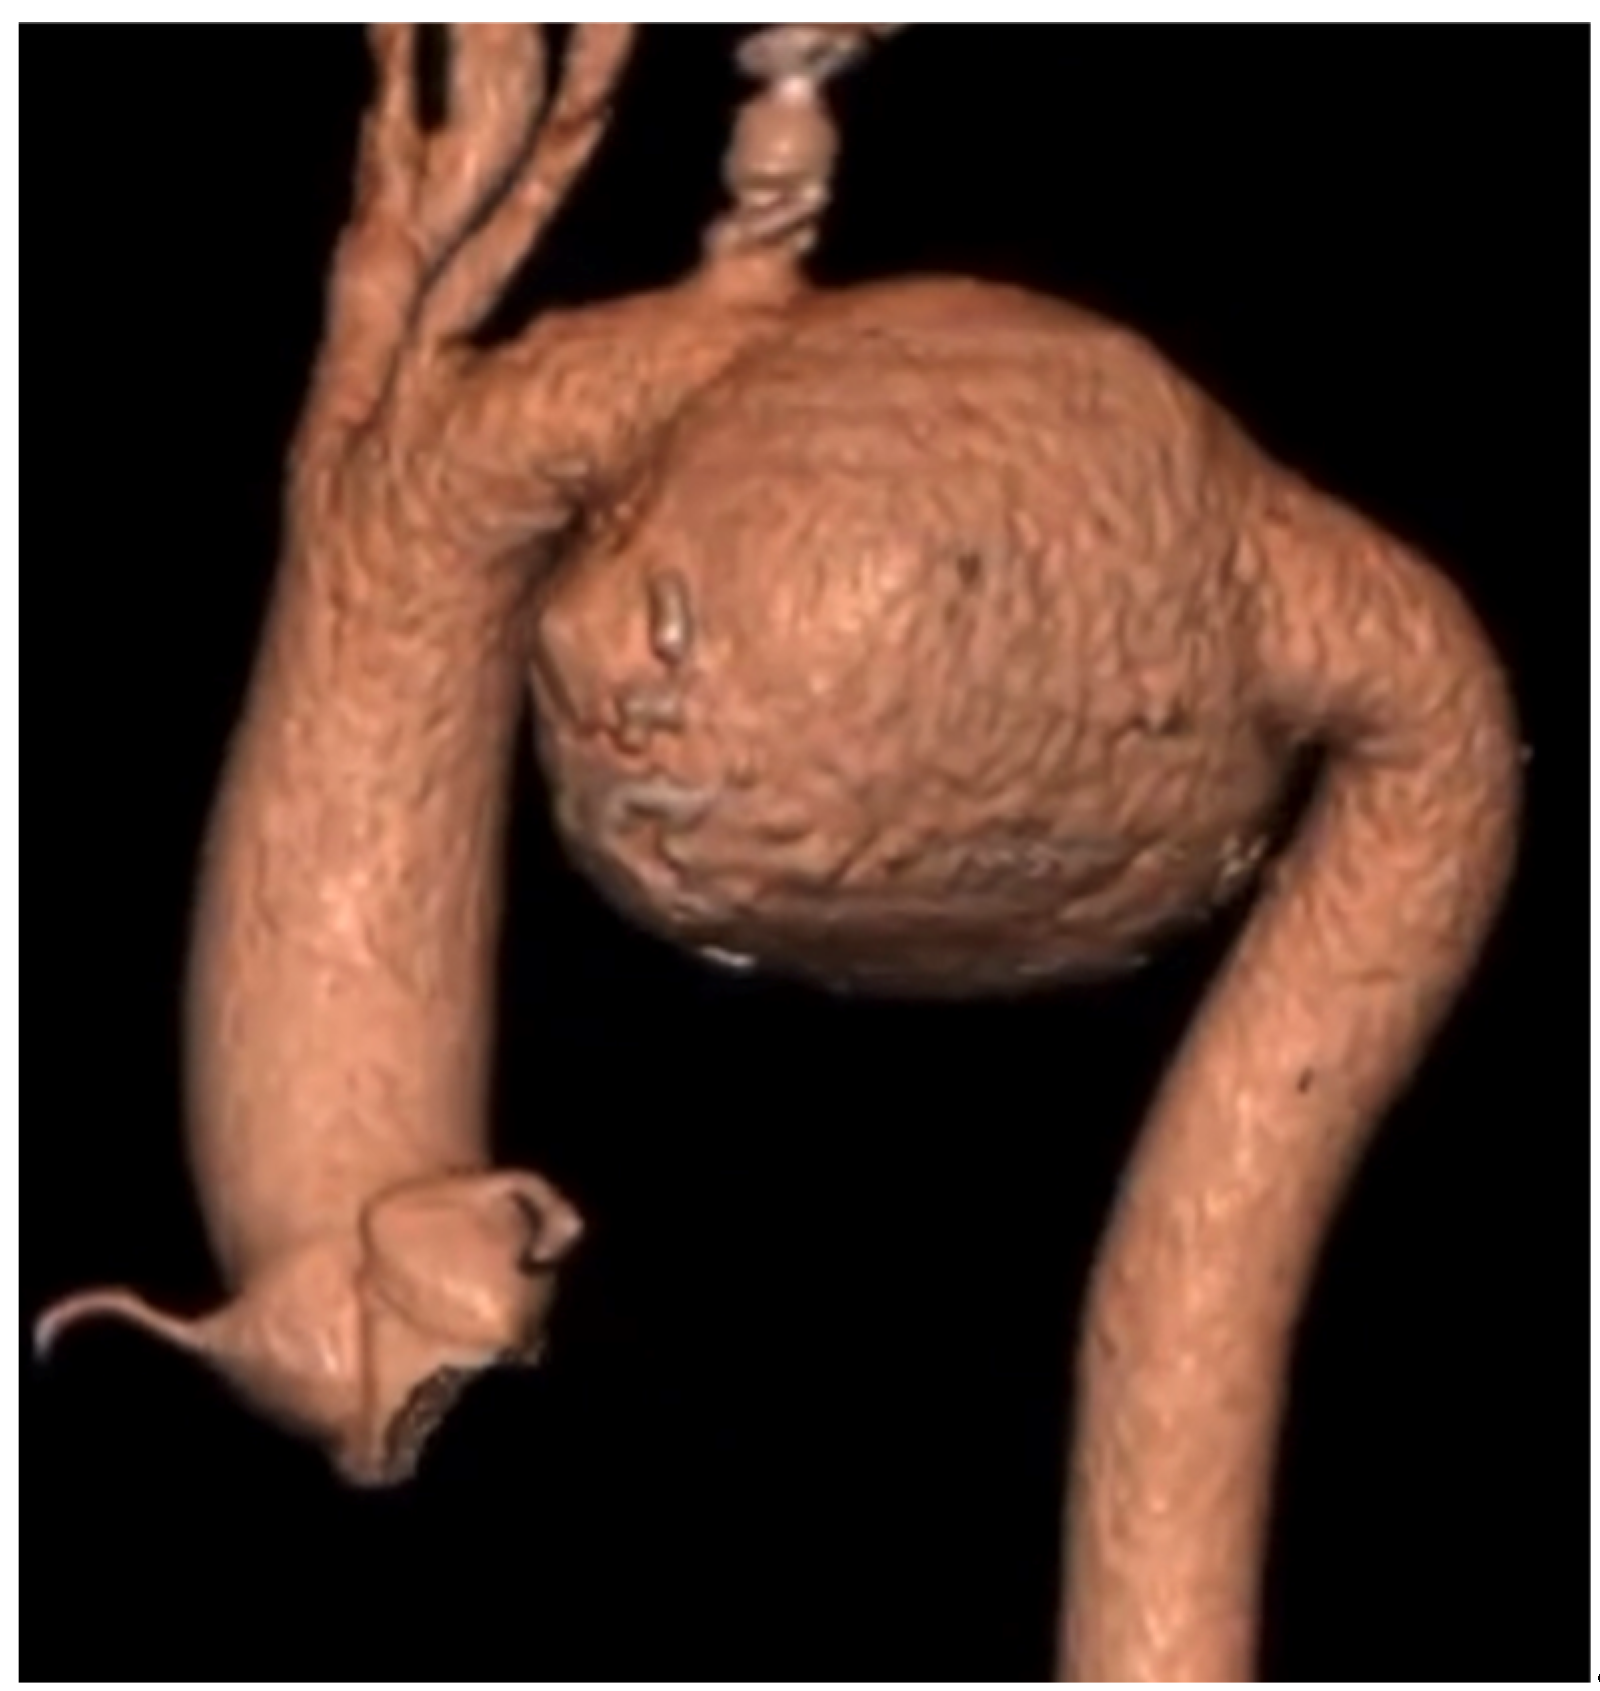

2.2. Case 2

| Current Case-2 | 46 | M | Aortic arch | Asymptomatic | 21 years | Hybrid (carotid-subclavian bypass + TEVAR) |